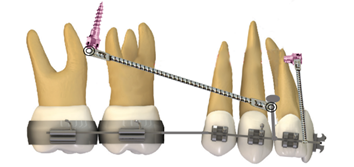

Camuflaje con propulsores FRD con anclaje de miniplaca

A pesar de ser una técnica relativamente nueva, el uso del dispositivo de resistencia a la fatiga (FDR) con anclaje de miniplaca, la inclinación labial desfavorable de los incisivos mandibulares se minimiza con la eficacia de las miniplacas, sin embargo, la corrección de la sobremordida horizontal y molar se da netamente a nivel dentoalveolar.

Su uso es para pacientes con maloclusión esquelética Clase II por una retrusión mandibular, utilizando el FRD con el anclaje mediante miniplaca. Se colocan aparatos fijos con ranura de 0,022 pulgadas sólo en los dientes superiores, después de ocho meses de nivelación y alineación de la arcada superior, se inserta un arco de acero inoxidable de 0,019 × 0,025 pulgadas y se cincha en la parte posterior 16.

Dos semanas después de la colocación de las miniplacas bilateralmente en la sínfisis y fijadas mediante tornillos de osteointegración de titanio (longitud, 7,0 mm; diámetro, 2,0 mm), se ajusta el FRD a las miniplacas con una varilla de 35 mm de longitud, los controles se lo realizan mensualente. Nueve meses después del uso del FRD anclado al esqueleto, se logran relaciones caninas y molares de Clase I y se elimina la sobremordida horizontal aumentada.

Este método influye en el crecimiento maxilar con un movimiento hacia delante mandibular y por lo tanto la corrección de la maloclusión Clase II 16.

Figura 7. Procedimiento para la colocación de miniplacas.

Elaboración: Los autores.